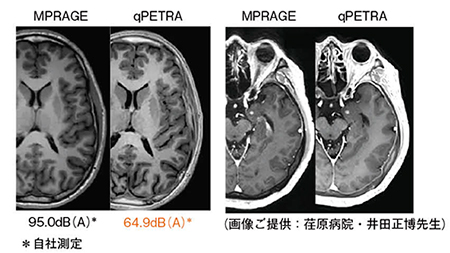

ここで,qPETRAの症例を提示する(図7)。従来のMPRAGEとqPETRAによる3D T1強調画像の比較を示している。静音効果は,従来法と比べて自社比で90%以上低減されていることがわかる。また,qPETRAは静音性だけでなく,prep IRを対象の組織のT1値に合わせたInversion Timeに設定することで,従来よりも高いT1コントラストが得られていることがわかる。

図7 頭部ルーチンMRI

3D T1強調画像